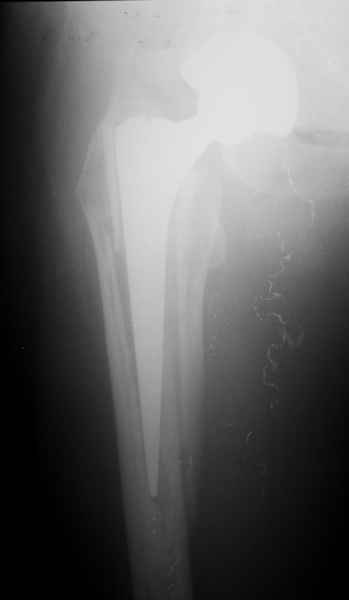

Хочется показать два подобных случая, П-ка З. 72 лет и п-т Г. 80 лет. Сразу принимаю замечание, что это были ножки цементной фиксации, просто под руками не было бесцементника.